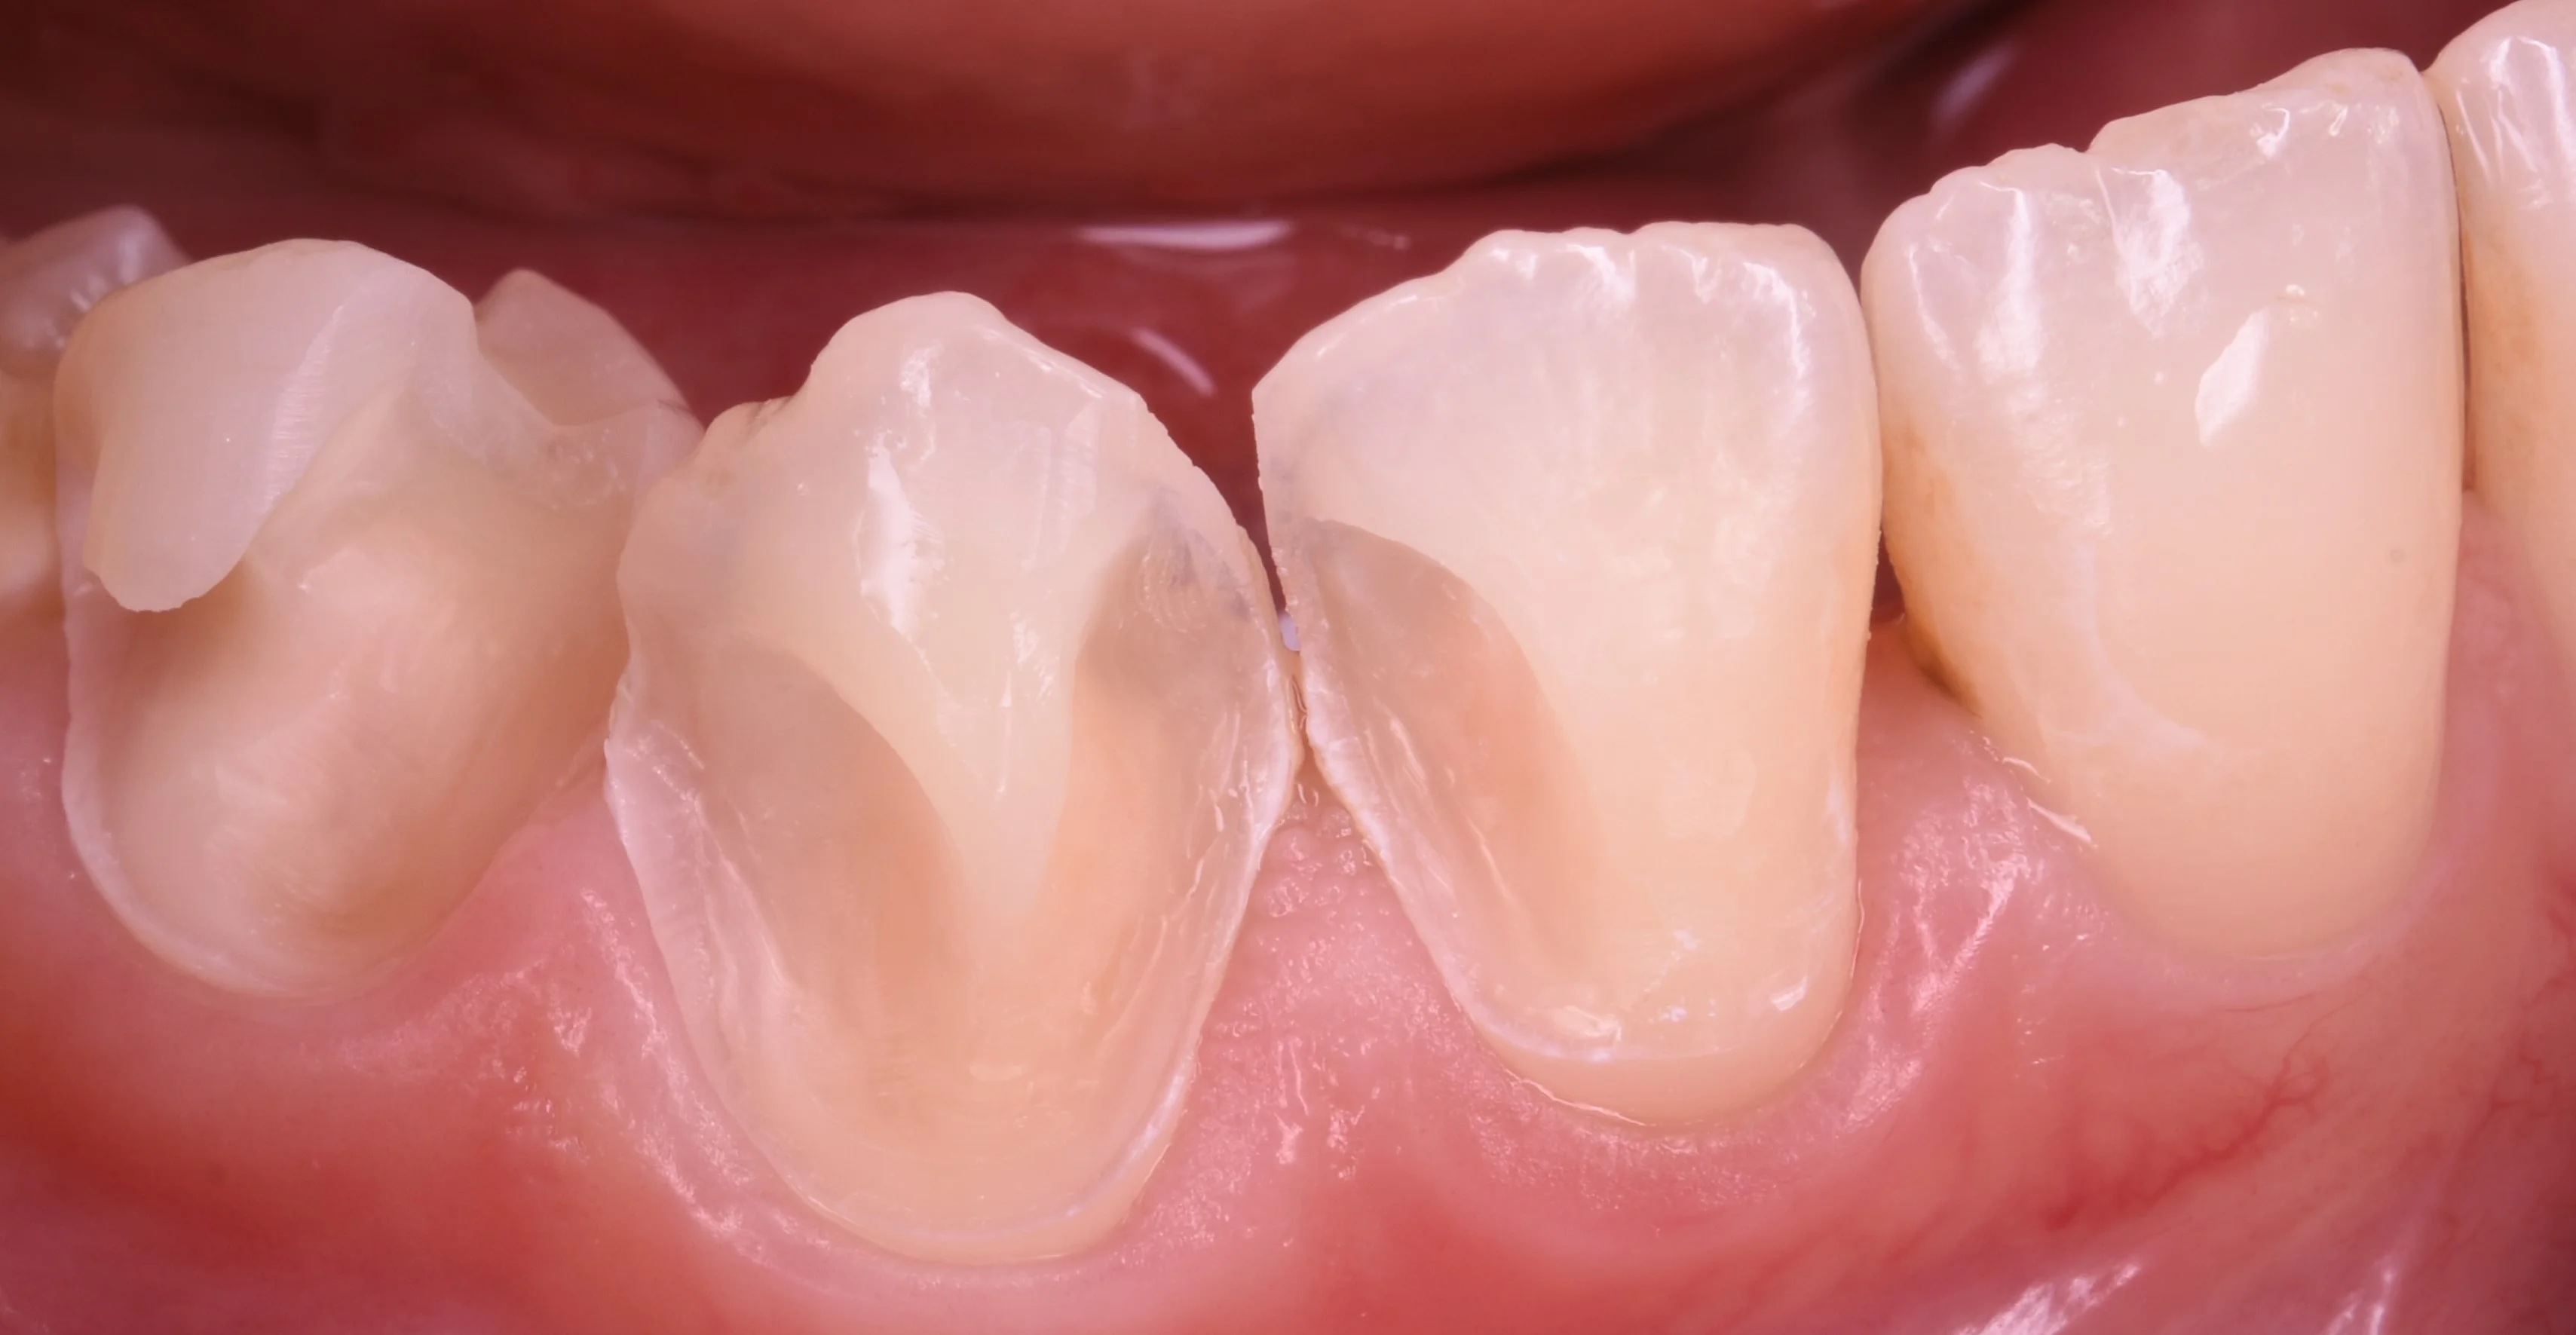

では術前の写真からです。

歯の側面が大きく虫歯になってしまっている状況ですね。

この虫歯の出来方はよく「初期の虫歯の状態で矯正のブラケットを装着した部分」で起こってくる印象です。

歯ブラシを届きやすくするためであったり、見た目を良くするために矯正を行なっても、ここまで大きく虫歯ができてしまうと少し勿体無いですね。

ブラケットを装着時は今までよりも歯磨きがしづらくなるため、虫歯や歯周病が悪化しやすい傾向にあります。

そのため、矯正の前には必ず虫歯や歯周病はない状態に治療を完了させておく必要があります。

矯正を考えられている方は必ず最初に矯正歯科ではなく「一般歯科」をまずは受診するようにしてくださいね。

或いは一般歯科を行なっている矯正歯科でもいいと思います。